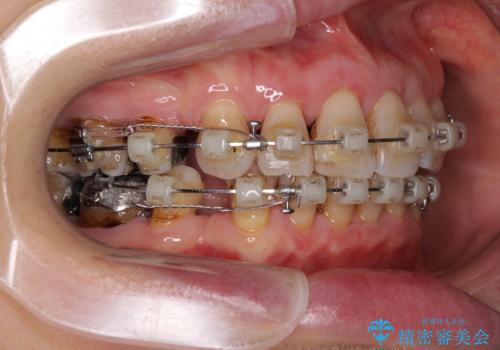

- 矯正装置

- クリアブラケット

- 突出した口元を引っ込めることを希望して来院された患者様です。

上下左右第一小臼歯4本を抜歯して、口元を改善するワイヤー矯正を行うこととしました。